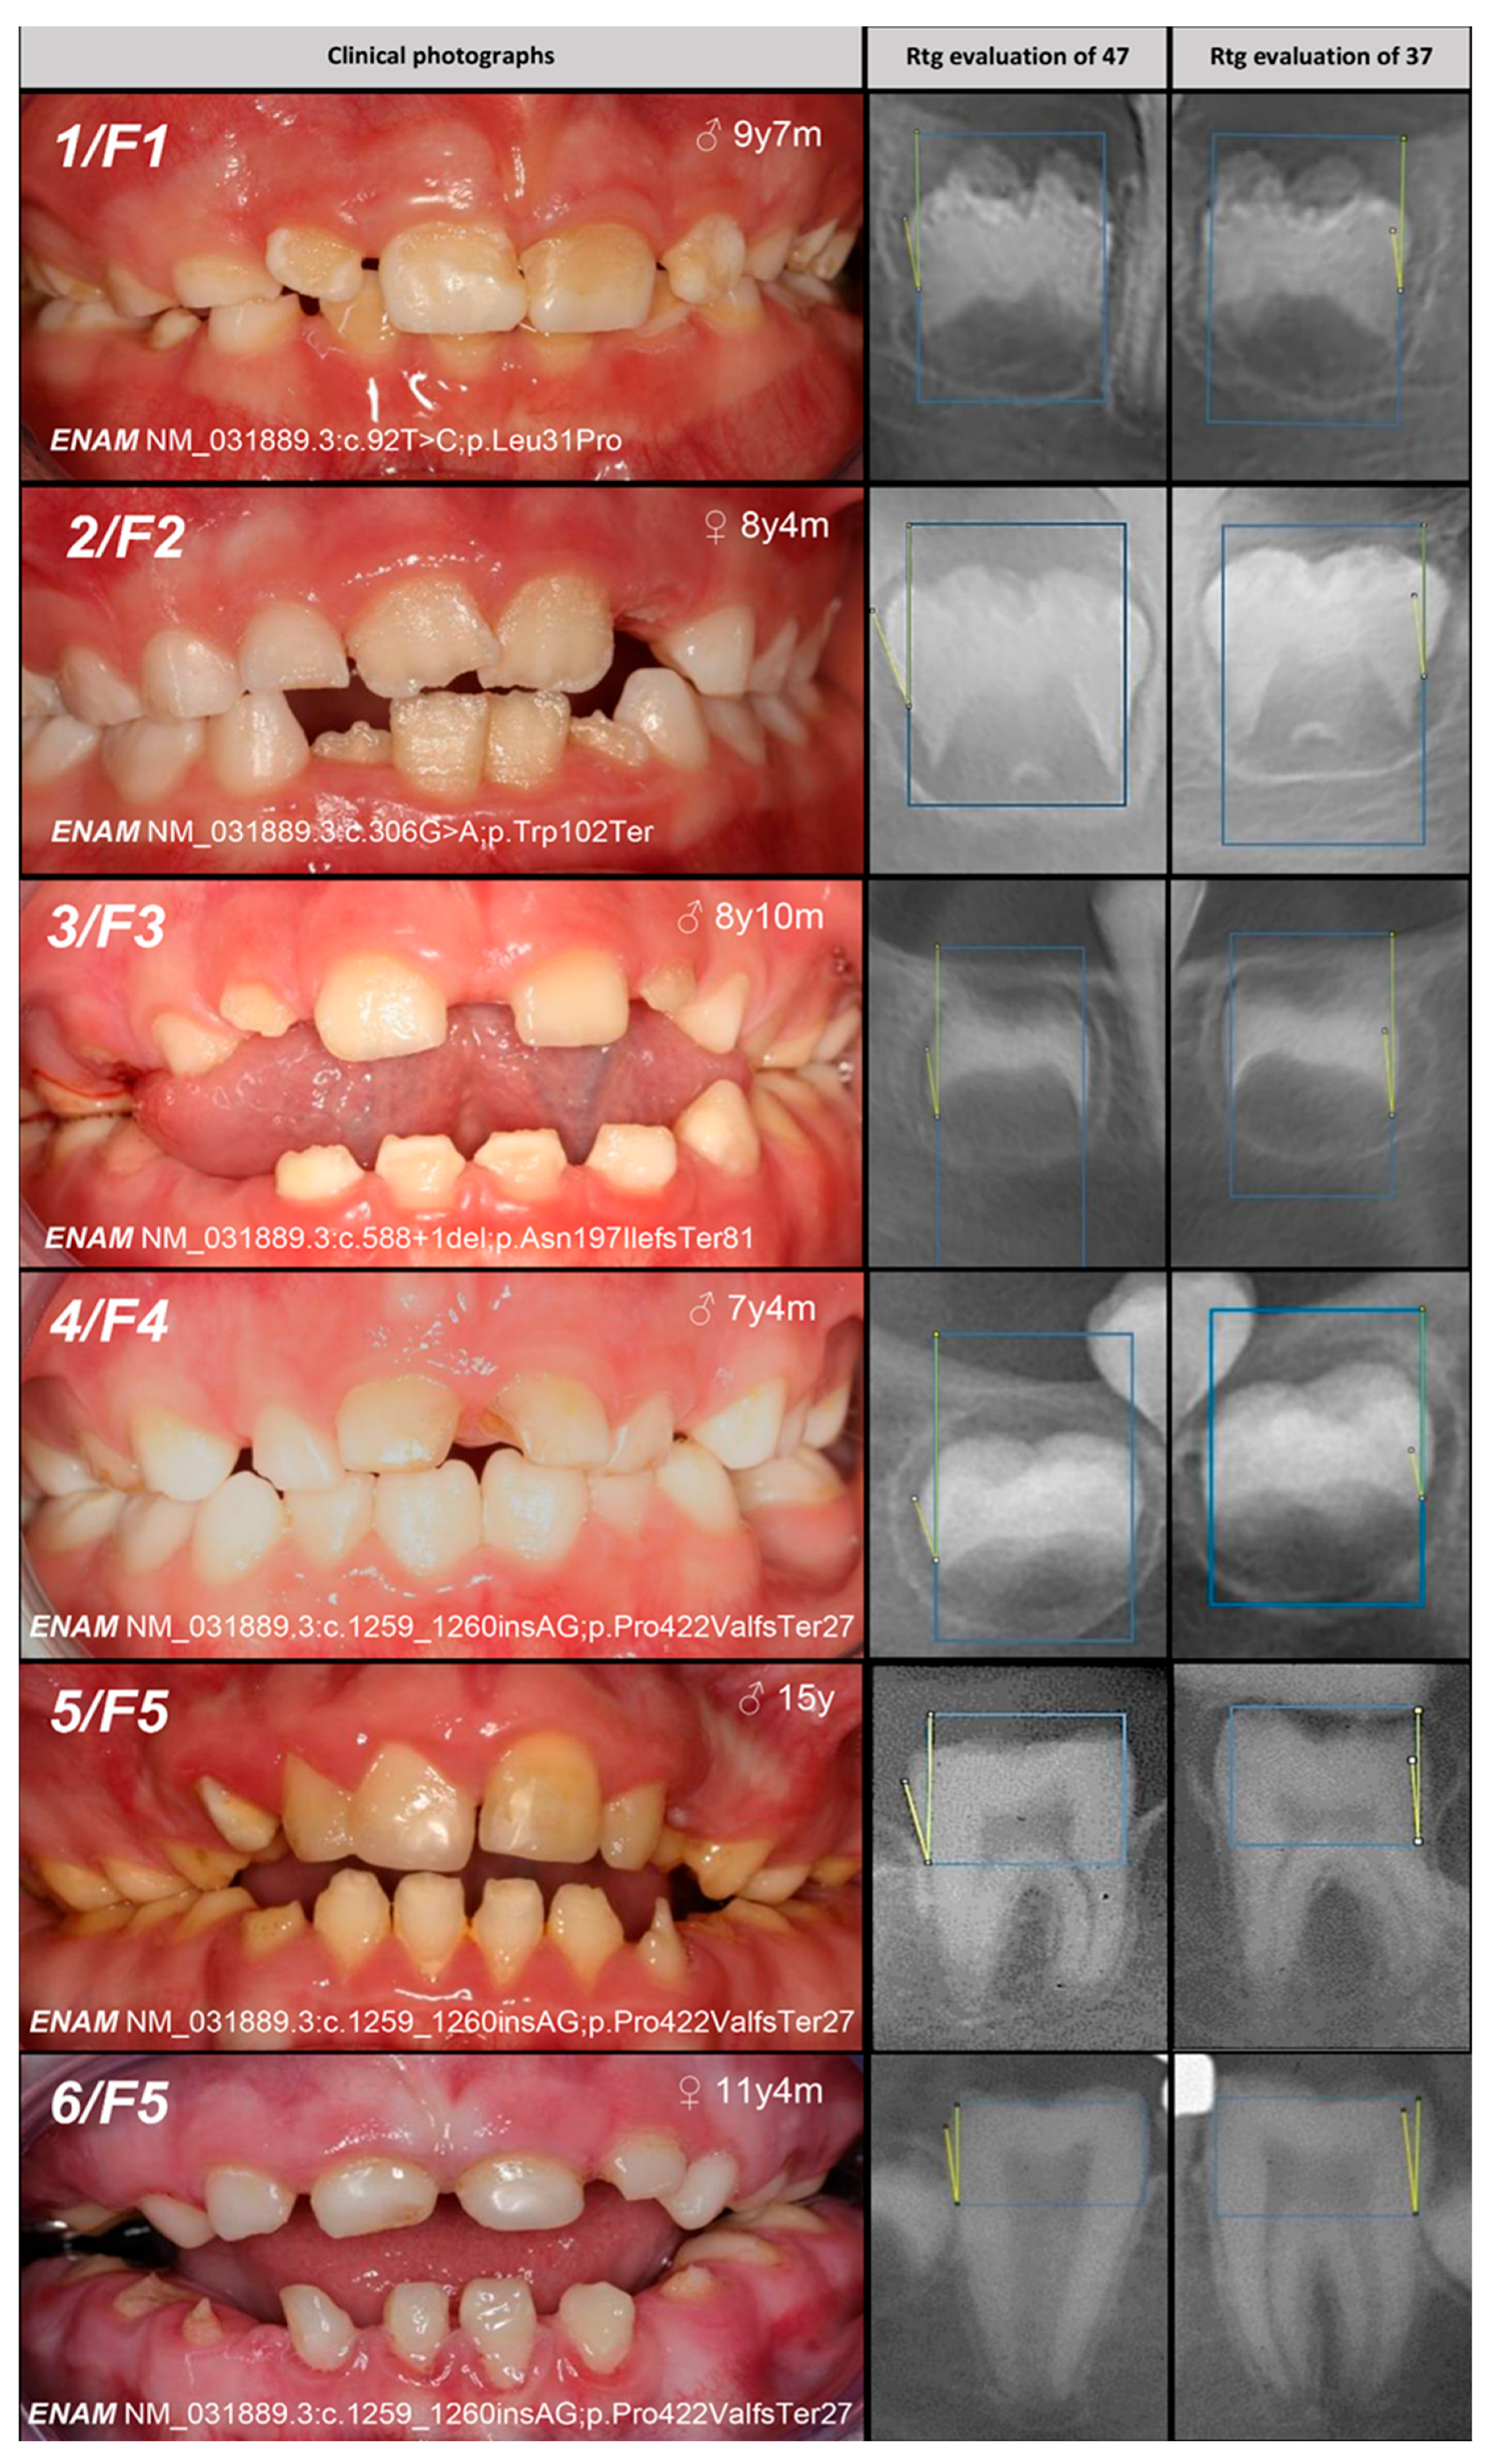

| Patient (n) Family (n) | Phenotype | OMIM, Mode of Inheritance, Gene Affected | Gene Variant | Zyg. | Protein Outcome | References | Fam. Segreg. | ACMG |

|---|---|---|---|---|---|---|---|---|

| 1, F1 | Hypoplastic (localized) | IB, AD, ENAM | c.92T>C | +/− | p.Leu31Pro | novel | Mo (AC) Fa (U) | likely pathogenic (PP1:moderate, PM5:moderate, PM2:moderate) |

| 2, F2 | c.306G>A | +/− | p.Trp102Ter | novel | Mo (AC) FaS (U) | likely pathogenic (PVS1:very strong, PM2:moderate) * | ||

| 3, F3 | Hypoplastic (generalized) | c.588+1del | +/− | p.? | [25] | Mo (U) Fa (AC) | pathogenic (PS4:strong, PVS1:strong, PM2:moderate) | |

| 4, F4 | Hypomineralized (hypoplastic) | IB, AD, ENAM | c.1259_1260insAG | +/− | p.Pro422Val fsTer27 | [5] | Mo (AC) FaS (U) | pathogenic (PS4:strong, PVS1:strong, PM2:moderate) GnomAD: 0.0002517 |

| 5, 6, F5 | Hypoplastic (generalized—recessive trait; localized, pitting, grooving—dominant trait) | IC, AR/AD, ENAM | −/− | [25] | MoFa (UC) | |||

| 7, F6 | MoFaS (UC) | |||||||

| 8, F7 | MoFa (UC) | |||||||

| 9, F8 | MoFa (UC) | |||||||

| 10, 11, F9 | Hypomineralized (heterogeneity) | IE, XLD, AMELX | c.103-3T>C | +/− | p.? | [26] | Mo(U) Fa (AC) | likely pathogenic (PP1:strong, PM2:moderate)* |

| 12, F10 | +/− | Mo (AC) Fa (NA) | ||||||

| and IIIA, AD, FAM83H | c.2363G>A | +/− | p.Ser788Asn | [26] | benign (BA1:stand-alone, BS2:strong, BP4:supporting, BP6:strong) | |||

| 13, F11 | Hypoplastic (heterogeneity) | IE, XLD, AMELX | c.485delT | 0/− | p.Phe162SerfsTer13 | novel | MoS (A) Fa (NA) | likely pathogenic (PVS1:very strong, PM2:moderate) |